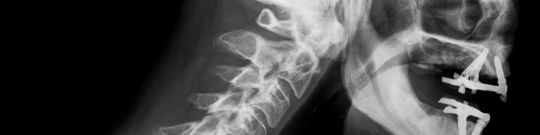

Anatomía de las vértebras cervicales Las vértebras de la columna cervical, representan la región más móvil y vulnerable de la columna. Ahora bien, debemos comprender que la columna cervical inicia desde la base del cráneo y está compuesta por siete vértebras.

La función de la columna cervical es contener y proteger la médula espinal, también brinda soporte al cráneo y permite los diversos movimientos de la cabeza.

Las vértebras cervicales son las más pequeñas y móviles de la columna, compuesta por C1-C2-C3-C4-C5-C6-C7…

Adicional a esto, el diagnóstico por imagen es importante, se recomiendan estudios de imagenología, tales como Radiografías, Tomografía Axial Computarizada o Resonancia Magnética.